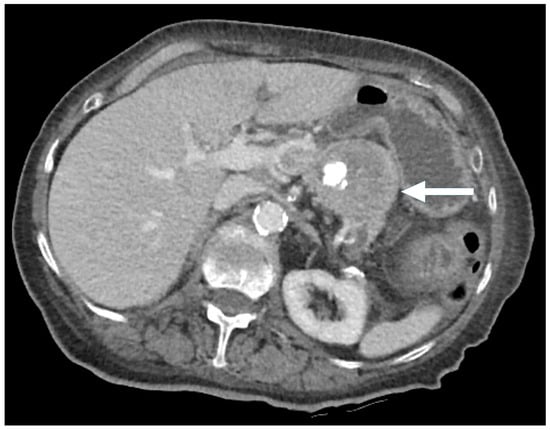

Figure 8. An 86-year-old female presenting with hypercalcemia and fatigue. CT: Pancreatic tail mass with mixed solid and cystic/necrotic components (arrow), along with focal gross calcification.

Figure 9. An 86-year-old female presenting with hypercalcemia and fatigue. H&E stain (left): Liver core biopsy showing a Grade 2 pancreatic neuroendocrine tumor (PNEN) with nested architecture, minor nuclear variation, and moderate cytoplasm. Ki-67 immunohistochemistry (right): a 20% Ki-67 index, consistent with intermediate proliferative activity (×200 magnification).

In the cystic PNENs, 83% were Grade 1 and 17% were Grade 2. In contrast, the hypoenhancing PNENs demonstrated a more aggressive profile, with 60% classified as Grade 2 and 40% as poorly differentiated pancreatic neuroendocrine carcinomas (PNECs) (Table 3).